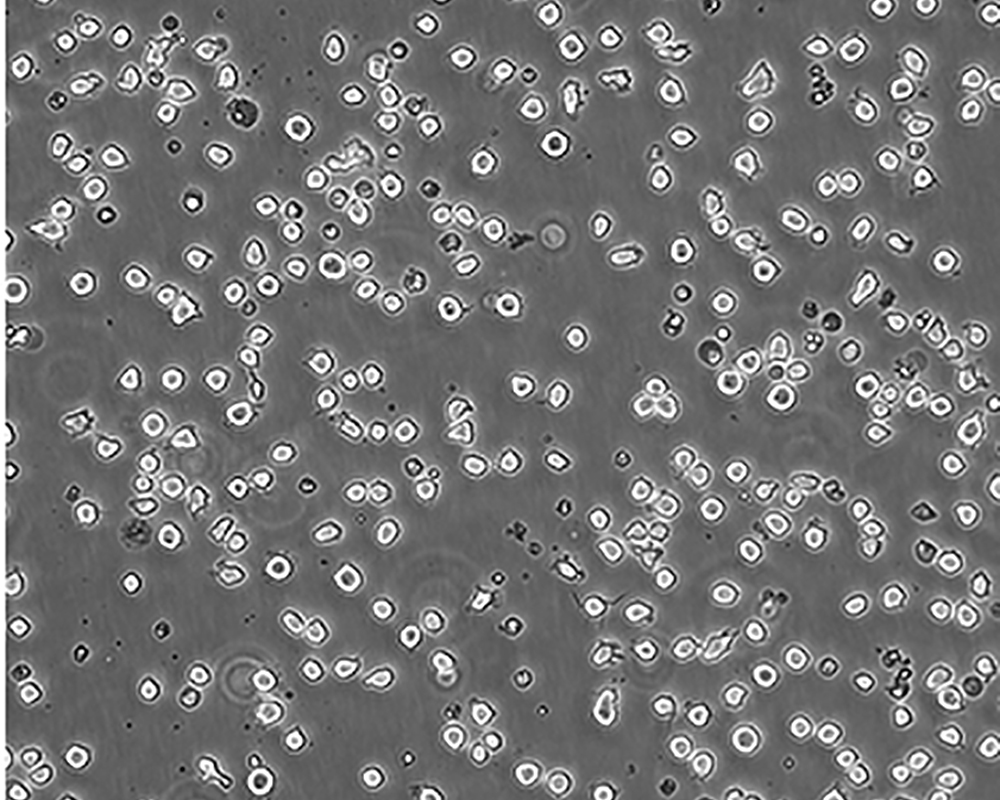

生長(zhǎng)特性 suspension

形態(tài)特征 monocyte

細(xì)胞描述 該細(xì)胞是由NilssonK實(shí)驗(yàn)室于1974年從一名37歲的患有惡性組織細(xì)胞性淋巴瘤的白人男性的胸水中分離建立的。1979年來(lái)的研究顯示該細(xì)胞在人混合淋巴細(xì)胞培養(yǎng)物上清、佛波酯、VitD3、γ-IFN、TNF和維A酸的誘導(dǎo)下可以向終末單核細(xì)胞分化。該細(xì)胞不合成免疫球蛋白,EBV陰性;可產(chǎn)生溶菌酶、β-2-微球蛋白,受PMA刺激后可產(chǎn)生TNF-α;表達(dá)C3R;可作轉(zhuǎn)染宿主;表達(dá)Fas,對(duì)TNF和抗Fas的抗體敏感。